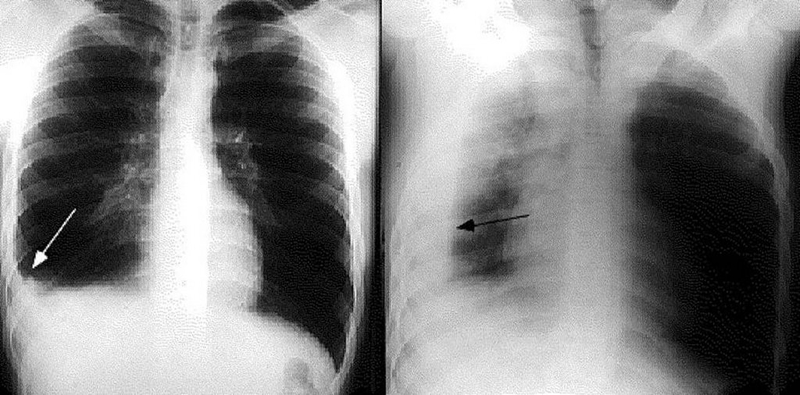

Xẹp phổi và tràn khí màng phổi là hai biến chứng nguy hiểm của viêm phế quản. Viêm phế quản khiến không khí đi vào phổi không thể lưu thông, bị tích tụ và ép vào phổi, khiến phổi bị xẹp một phần hoặc toàn bộ.

Hằng năm, tại Việt Nam, có đến 1.000 ca được chẩn đoán tràn dịch màng phổi. Đau ngực và ho là dấu hiệu đầu tiên của hội chứng tràn dịch màng phổi. Dấu hiệu này có thể tiến triển rất nhanh thành co giật, hôn mê, khó thở,... và cuối cùng là tử vong.

Viêm phổi rất dễ dẫn đến tràn dịch màng phổi

Nếu nghi ngờ bản thân bị viêm phế quản dù là ở thể nhẹ, bạn cũng nên đến gặp bác sĩ để được thăm khám và điều trị dứt điểm. Bằng các xét nghiệm, chụp X-quang, các bác sĩ sẽ biết được chính xác nguyên nhân gây bệnh và đưa ra phác đồ điều trị hiệu quả nhất. Thông thường, thuốc Tây y chữa viêm phế quản là các loại thuốc kháng sinh có tác dụng diệt khuẩn kết hợp với thuốc trị ho, long đờm, thuốc giảm ho, giảm sốt,...